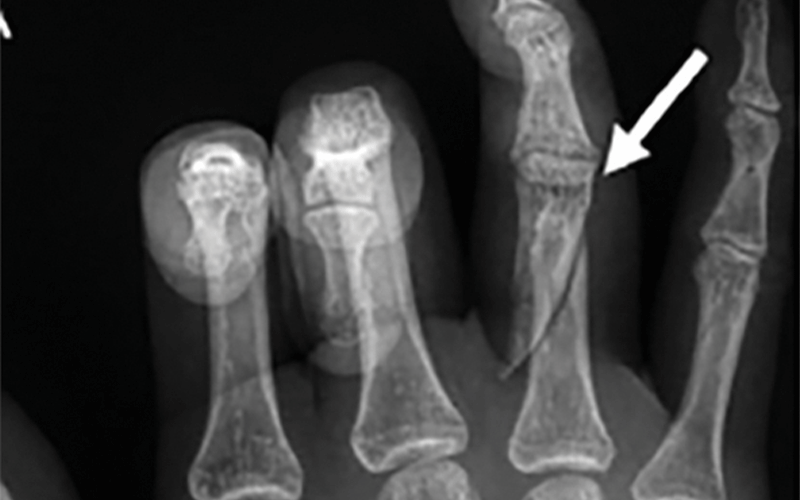

The study results offer radiologists clues as to exactly what to watch for. Acute fractures and obstetric/gynecologic complications — for instance, pregnancy loss and intrauterine growth restriction — were associated with greater odds of intimate partner violence.

Dr. Khurana immediately decided to conduct a study seeking to define injury patterns seen in intimate partner violence victims. She connected with colleagues at Brigham already working on the clinical and social aspects of intimate partner violence and inspired three radiology residents to collaborate on this under- explored topic for the Radiology study, “Radiologic Findings in Intimate Partner Violence.”